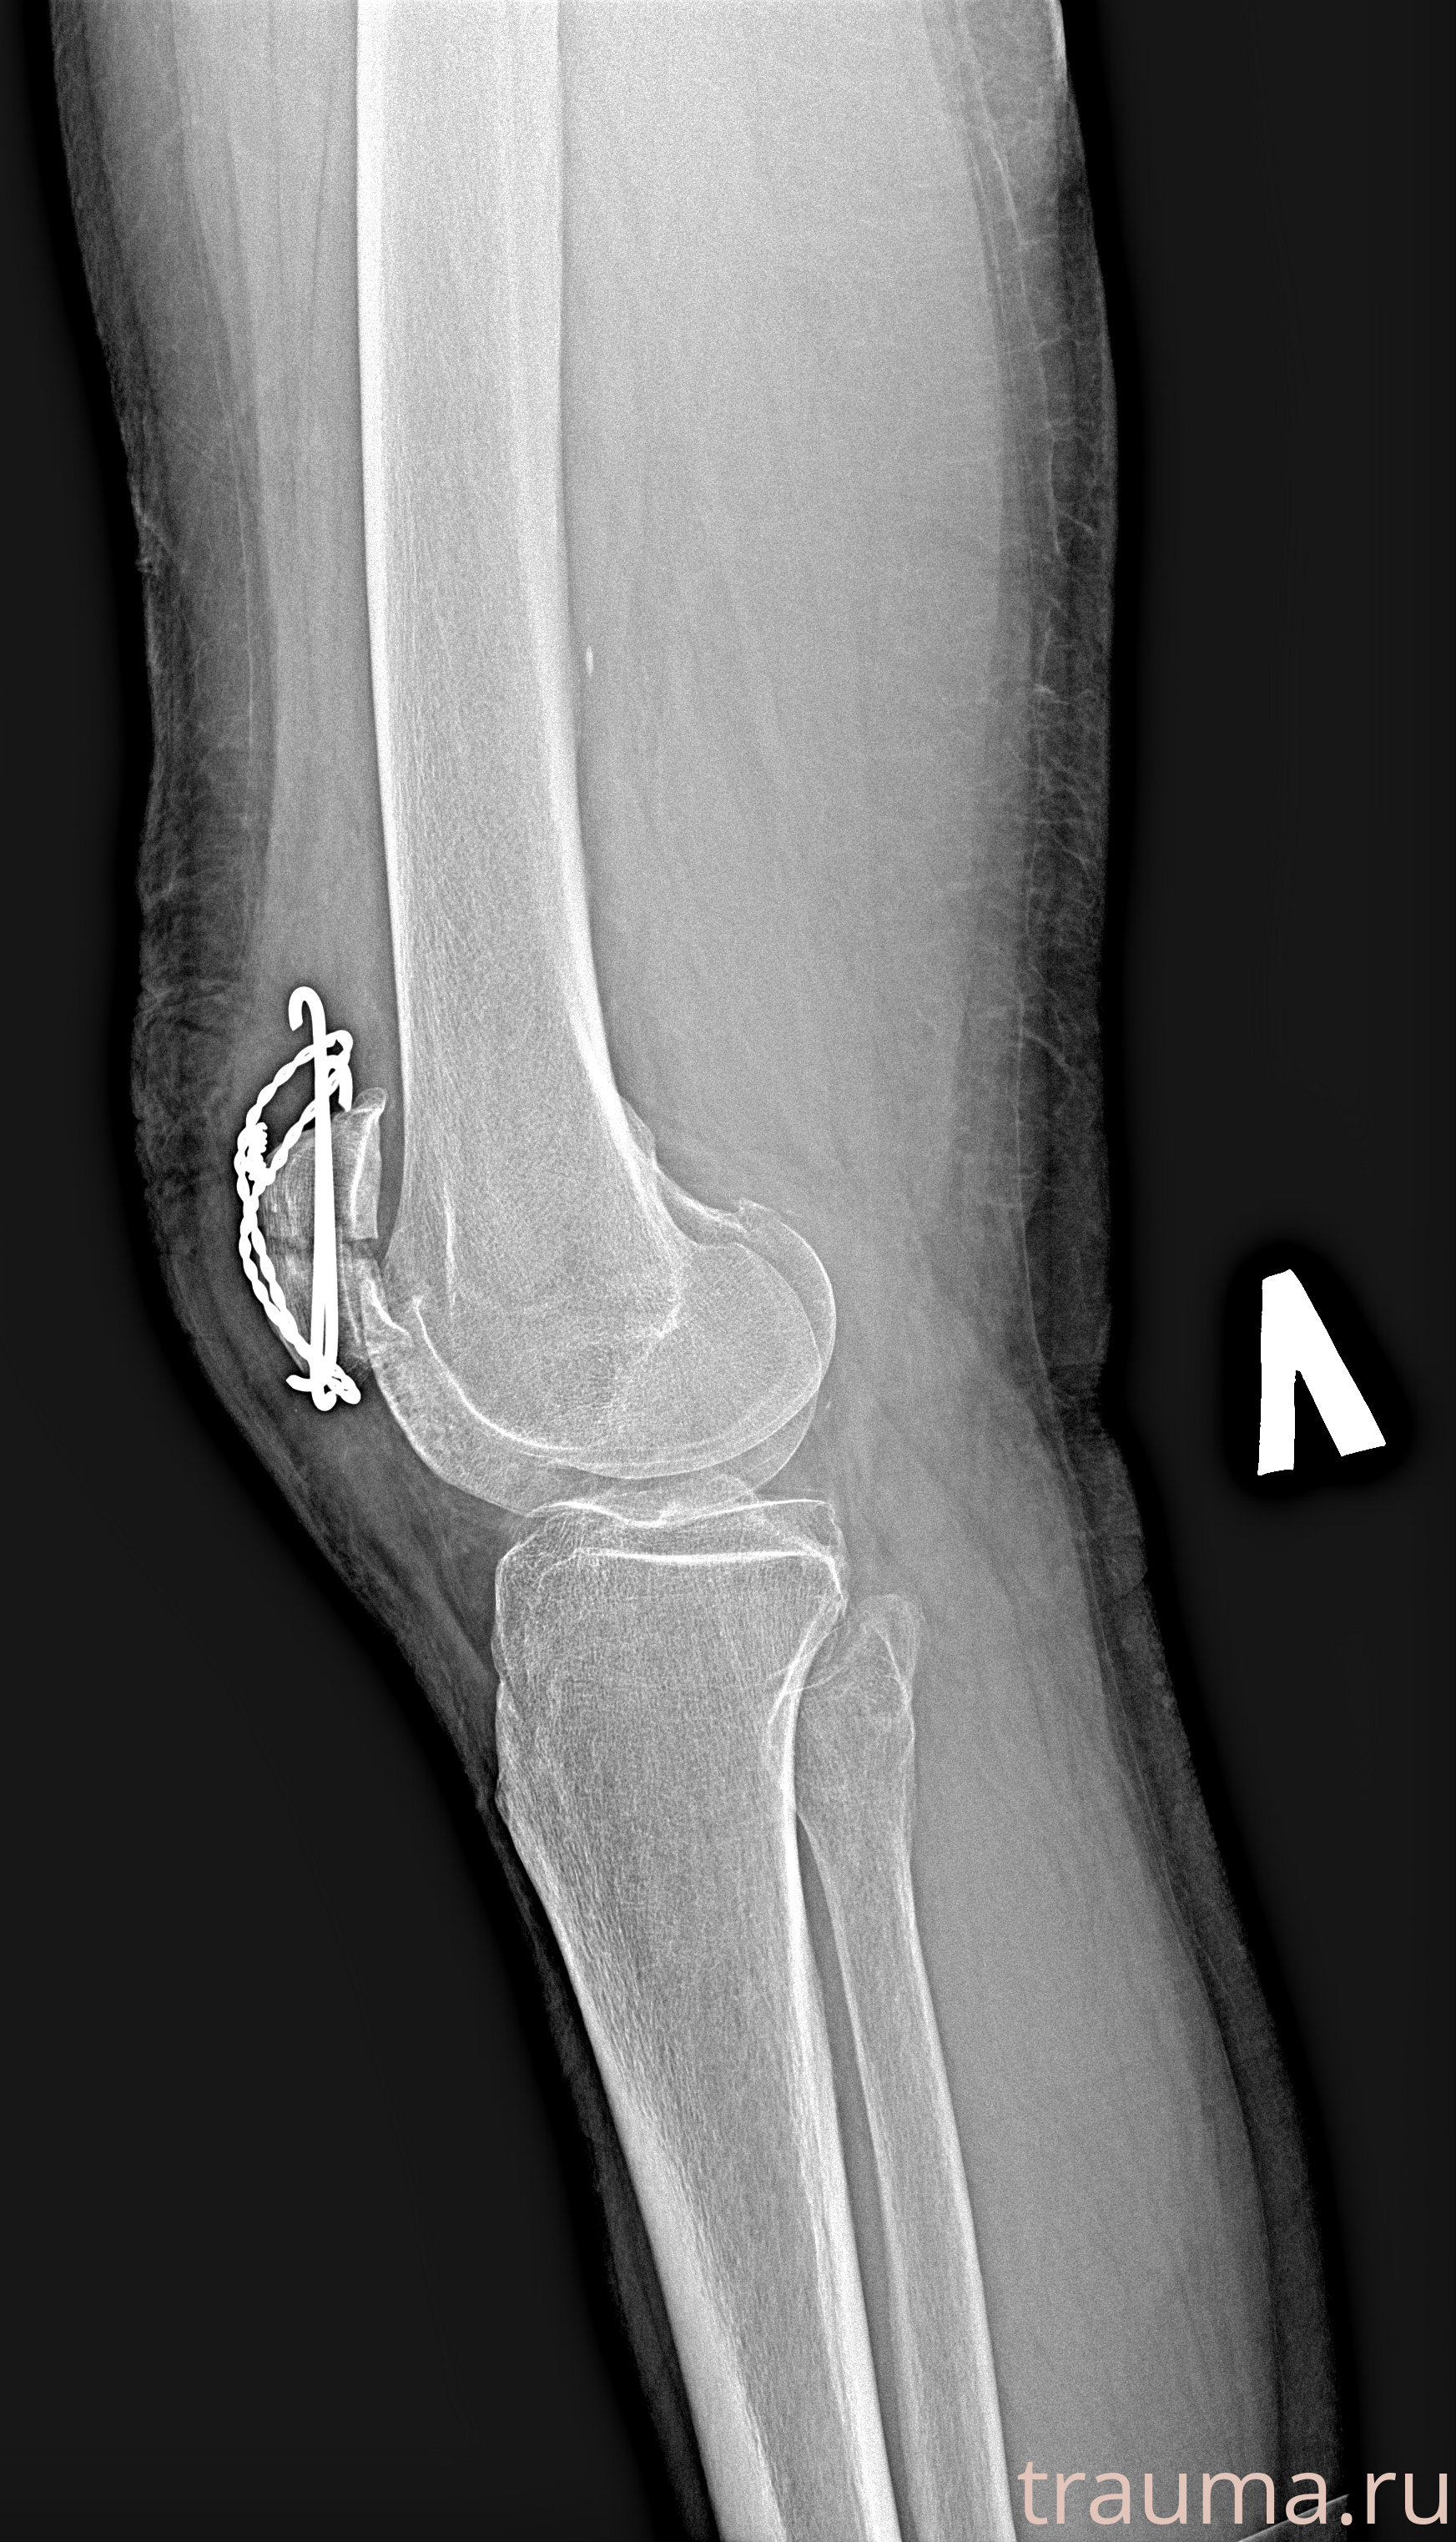

Рентгенограммы

Яркость: 1   Контраст: 1   Инвертировать: 0 Увеличение: 1

Перетаскивайте мышь вверх/вниз для контраста, влево/право для яркости. Прокрутка колесом изменяет масштаб. Нажмите Сбросить для возврата к исходному изображению. При увеличении держите мышь в той области, которую хотите рассмотреть.